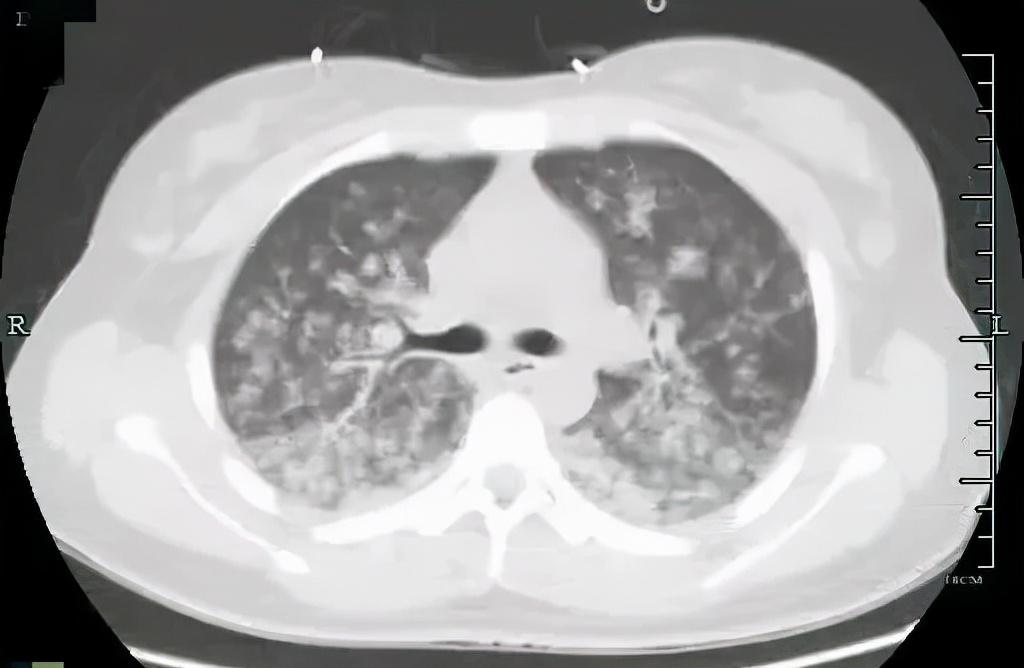

肺里一片“暴風(fēng)雪”

兩種原因造成的結(jié)果相似,但調(diào)節(jié)方案截然不同。根據(jù)小月的肺動(dòng)脈CTA、肺部CT等檢查結(jié)果顯示,小月為肺脂肪栓塞,此時(shí)小月的肺部已是白茫茫一片,就像暴風(fēng)雪一樣,脂肪進(jìn)入她肺部,刺激血管發(fā)生痙攣,產(chǎn)生嚴(yán)重的炎癥因子風(fēng)暴!

小月被迅速轉(zhuǎn)入ICU進(jìn)行救治,肺部的脂肪會(huì)被機(jī)體逐漸吸收,但由于造成嚴(yán)重炎癥,此時(shí)的生命支持調(diào)節(jié)就顯得尤為重要,ICU專家團(tuán)隊(duì)通過激素、抗凝、抑酸護(hù)胃、補(bǔ)液等一系列對(duì)癥調(diào)節(jié)后,小月的血氧飽和度漸漸恢復(fù)了正常?!拔覐恼吾t(yī)院開始就意識(shí)模模糊糊的,等我再次清醒過來時(shí),發(fā)現(xiàn)自己在ICU里了?!?/p>